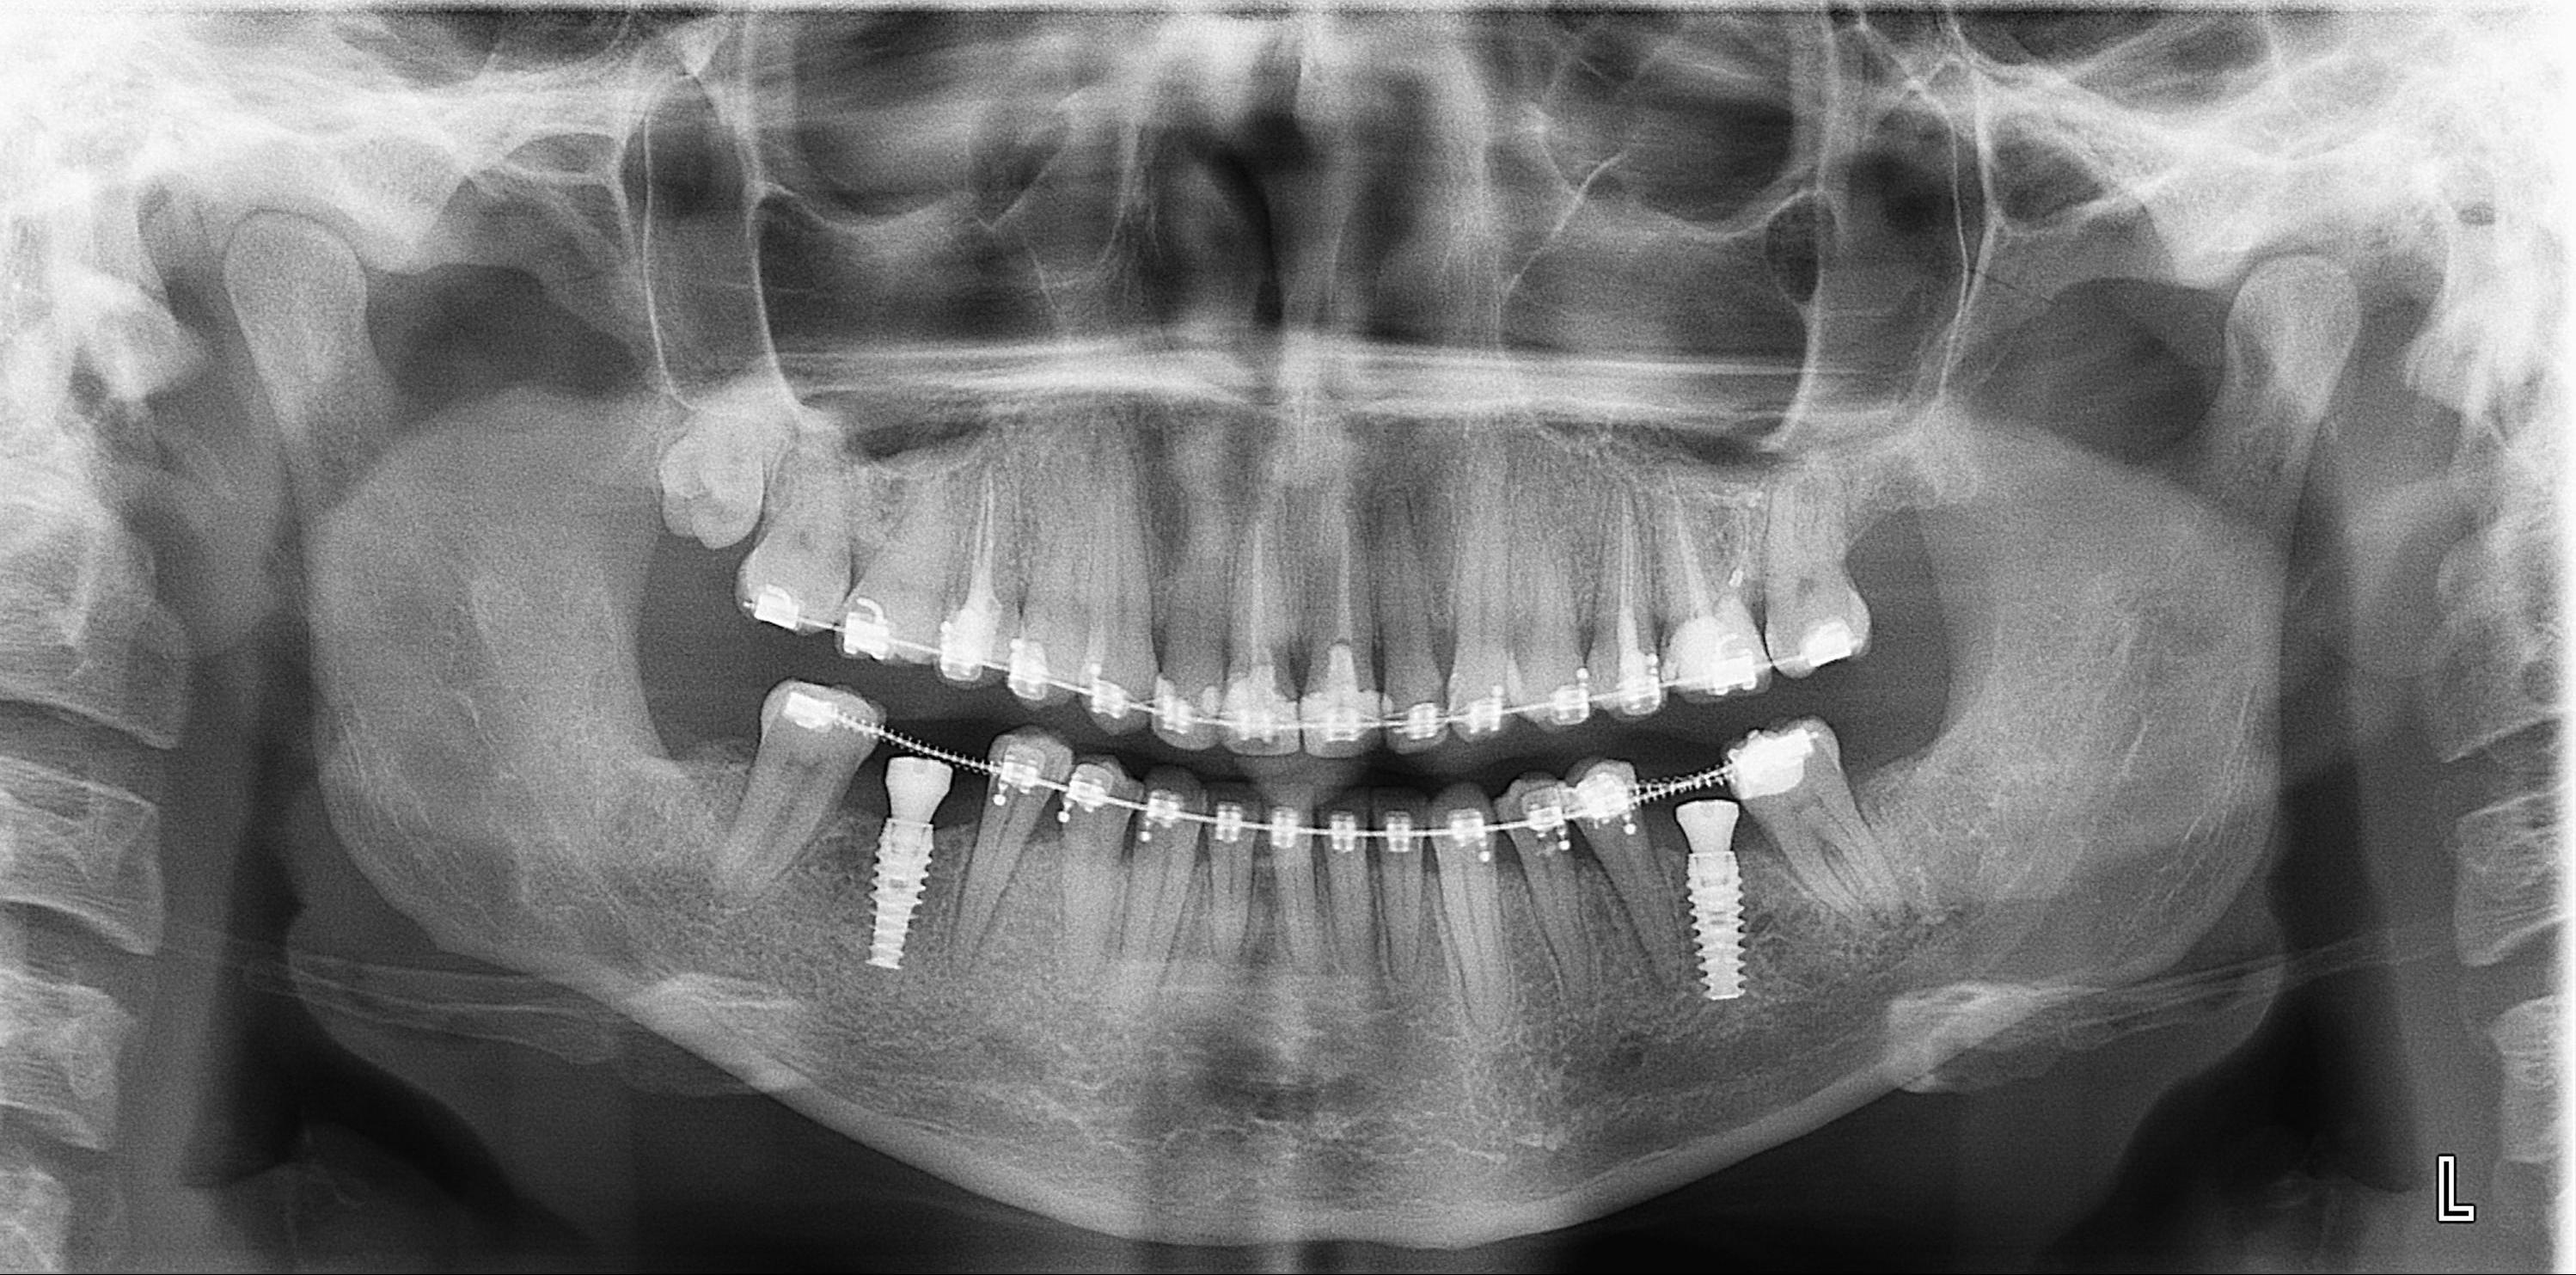

Дентальные снимки и диагностика кариеса